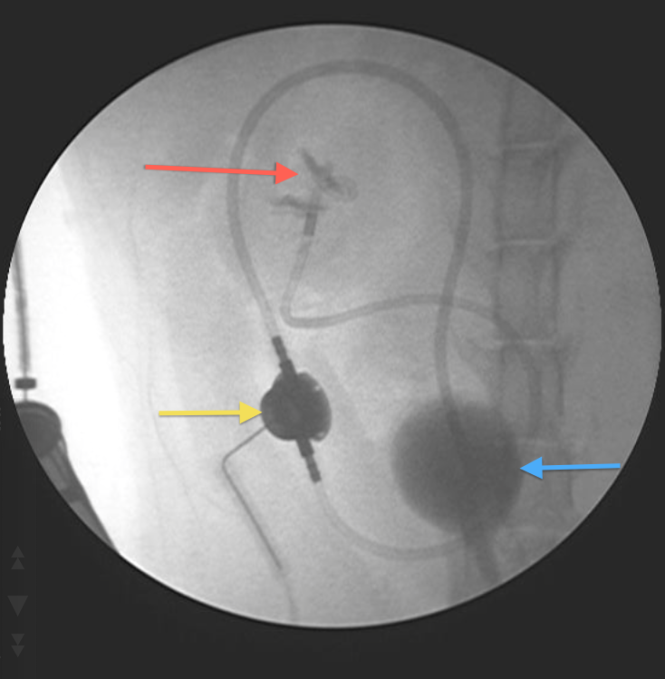

Fig 3: An intraoperative fluoroscopy picture confirming correct placement of the implants. Red arrow = pigtail nephrostomy tube within renal pelvis; Yellow arrow = access port; Blue arrow = bladder (containing contrast)